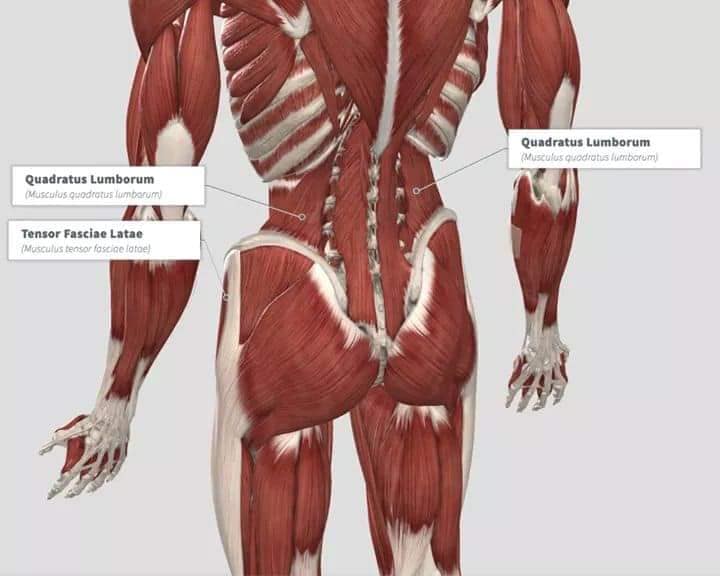

Спинні м'язи

Спинні м'язи виконують функції підтримки хребта, а також дозволяють здійснювати рухи тулуба.

Глибинні спинні м'язи

М'язи, що забезпечують стабільність хребта: М'язи, що розташовані між хребцями: включають мускулатуру, яка забезпечує стабільність і підтримку хребта, а також дозволяє здійснювати рухи хребта.

М'язи, що здійснюють ротацію та нахили

М'язи, що забезпечують ротацію хребта: Ротаційні м'язи: допомагають у здійсненні обертальних рухів тулуба, а також у підтримці рівноваги і стабільності хребта.